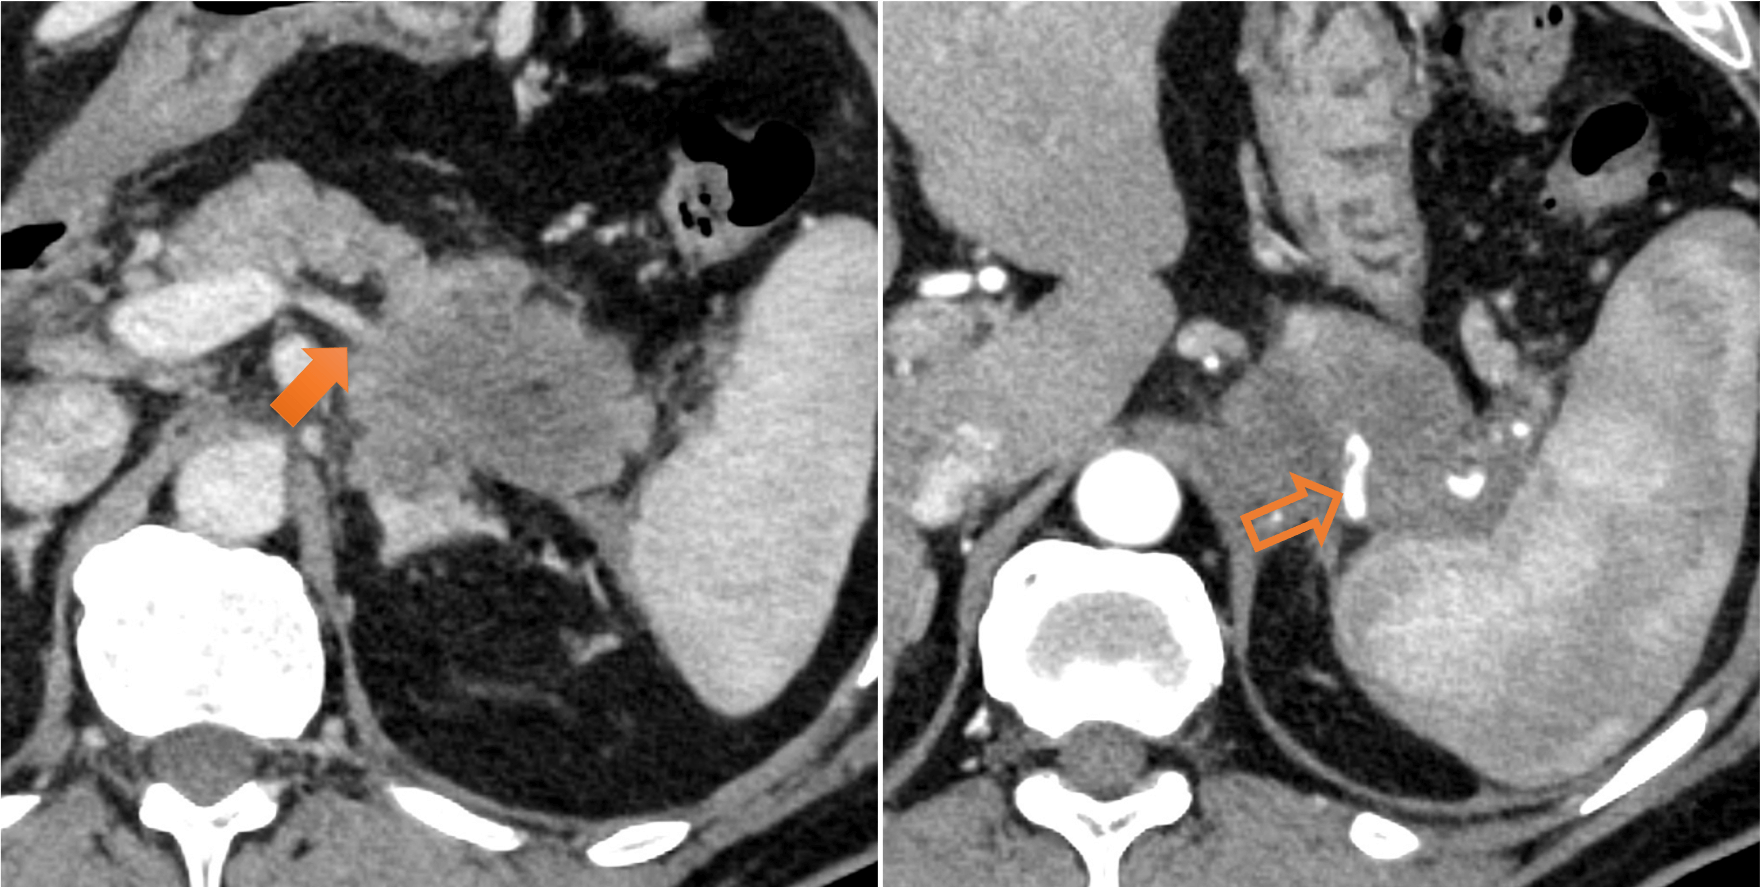

図1.膵尾部腫瘤(66mm)

膵尾部に漸増性の濃染を伴う乏血性腫瘤を認めた。膵尾部癌が疑われた。

図3.脾動静脈浸潤

脾静脈は腫瘍により閉塞しており(→)、脾動脈は腫瘍と全周性に接触し、口径不整を認めた(⇨)。